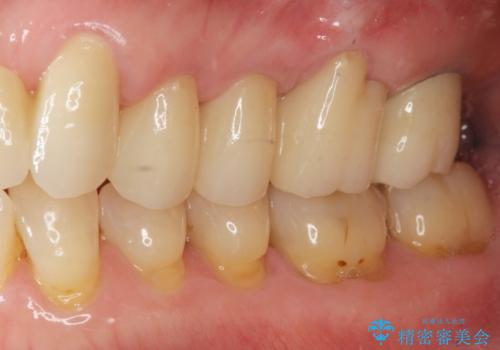

歯ぎしりに抵抗する歯周補綴 インプラント補綴

- 61万円(仮歯・フルジルコニアクラウン×4 ・インプラント・チタンカスタムアバットメント )費用は治療当時の料金となります

分岐部病変を併発していた歯は、抜歯としインプラントによる咬合機能の回復。残すことのできる歯は歯周治療後連結補綴を行い歯ぎしりに対抗します。

夜間のナイトガード装着は必須です。